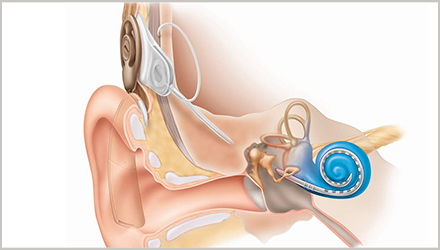

此外,对于部分助听器效果甚微或无效的听力损失,可以通过手术,植入人工耳蜗,绕过患者耳朵受损的部位,直接刺激耳蜗内的听毛细胞,让人们重获声音。

患有重度至极重度感音神经性听力损失的儿童和成人可以考虑通过植入人工耳蜗以恢复部分听力。

与传统放大声音的助听器不同,人工耳蜗绕过了听觉系统的受损部分,直接刺激听觉神经。

通常在助听器补偿没有太大效果的情况下,医生会建议选择人工耳蜗植入,在行手术前,需要由专业医院的专业医生对弱听人士的个人听力情况和健康状况做全面评估,符合植入标准的才能行手术。

人工耳蜗植入术是一种侵入性治疗,所以通常医生只对重度及以上的,助听器效果甚微或无效果的弱听人士提出手术建议。(更多关于人工耳蜗植入的适应信息,请点击回看往期文章“人工耳蜗适应症”)